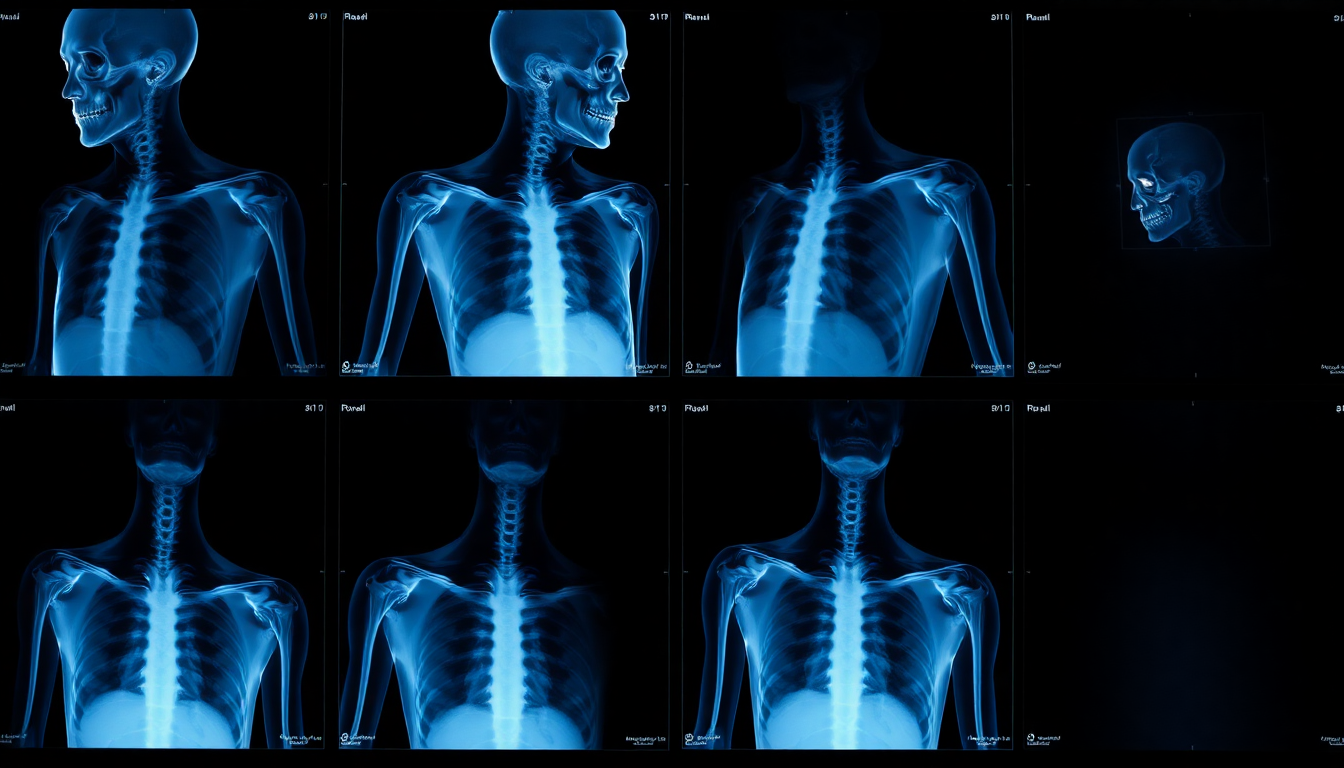

Evaluación Sistemática Paso a Paso

• 1. Huesos: verificar continuidad y acortamiento en clavícula y escápula.

• 2. Articulaciones: congruencia glenohumeral y espacio acromioclavicular.

• 3. Alineación: cabeza humeral centrada y comparación con lado sano.